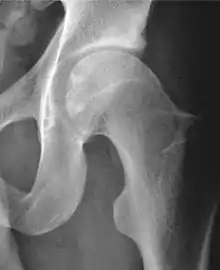

Projectional radiography ("X-ray")is often considered first line for FAI.[10] Anterior-posterior pelvis and a lateral image of the hip in question should be attained.[10] A 45-degree Dunn view is also recommended.[10][19]

| Alpha angle | ![]() |

Degree of bulging of the femoral head-neck junction: In normal conditions there is a symmetric concave contour at the junction of the femoral head and neck. Loss of this concavity or bone bulging may lead to cam type impingement. The degree of this deformity can be measured by the alpha angle. Although it can be measured in the cross-lateral view, the 45° Dunn view is considered more sensitive and the frog leg view more specific in determining pathologic values. |

|